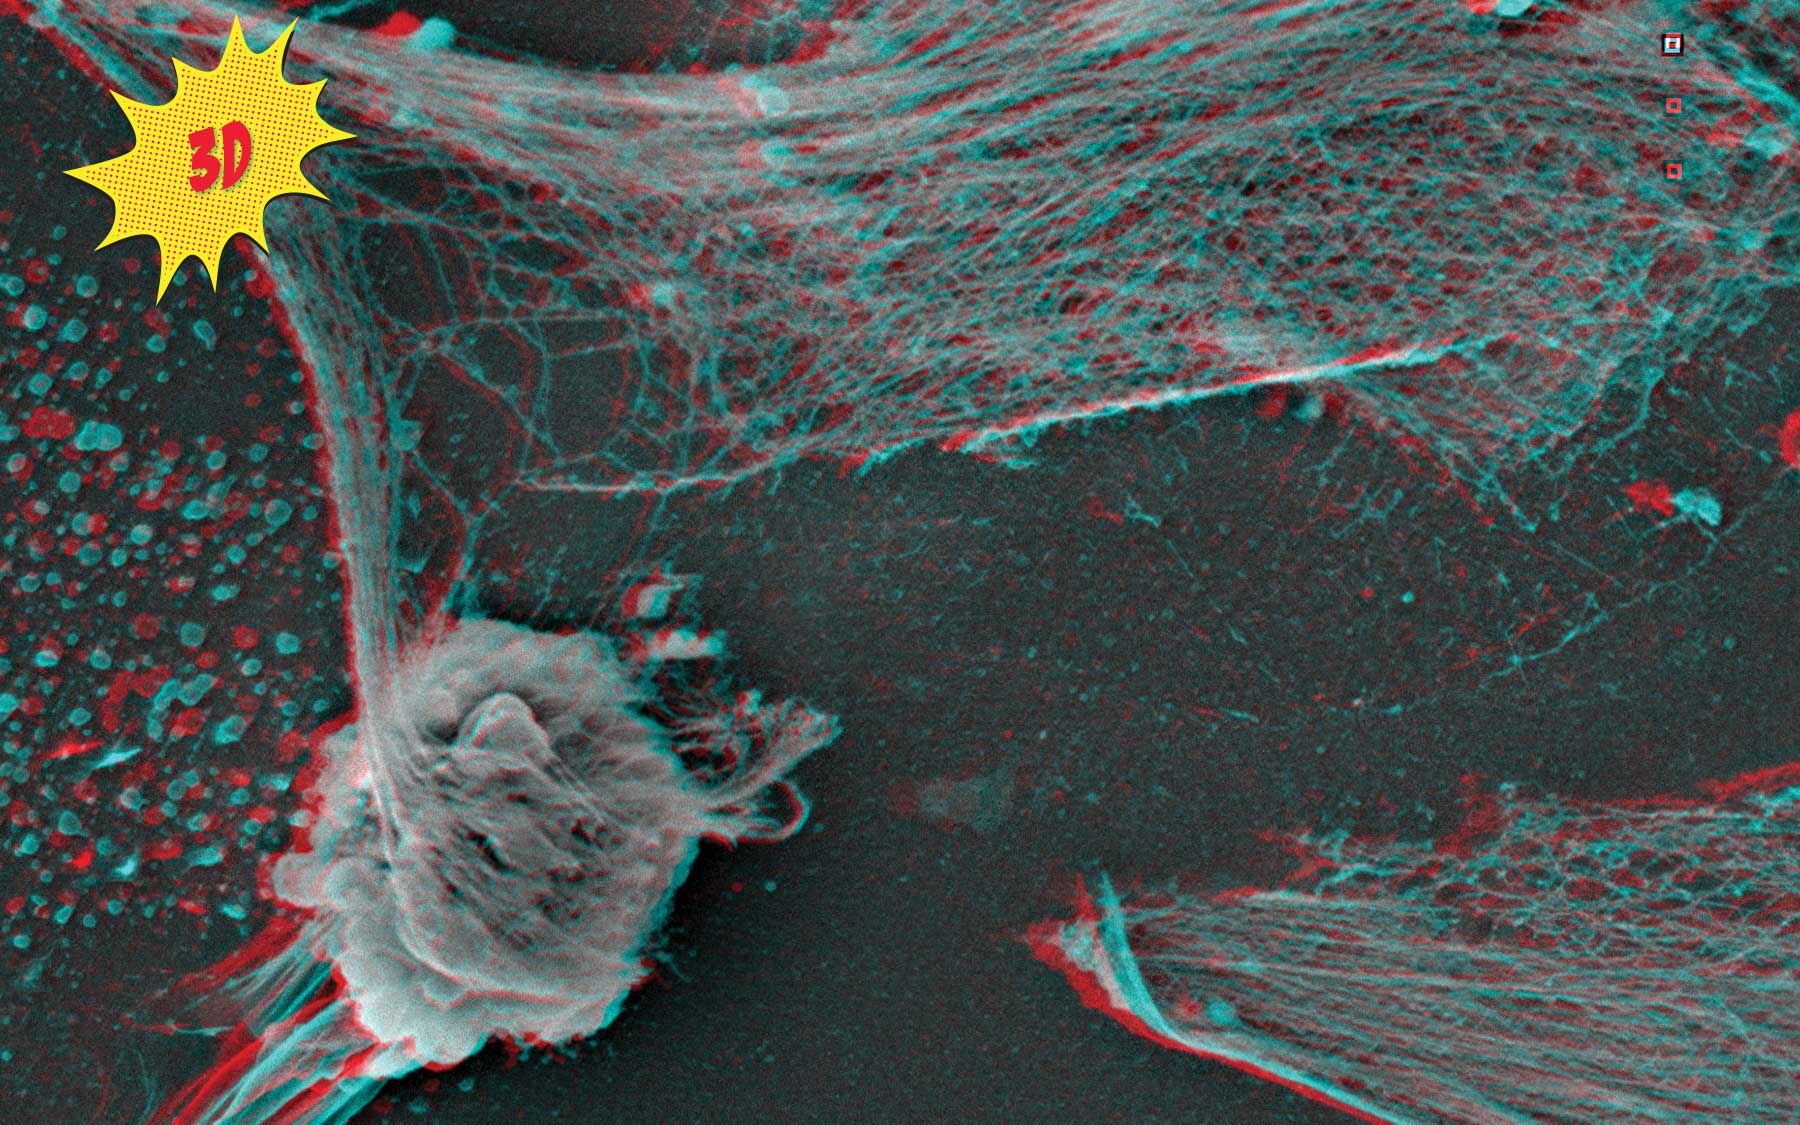

Cancer is infamous for repurposing molecules and mechanisms our body routinely uses to sustain itself. This remarkable 3D image, made by CSHL’s expert electron microscopist Stephen Hearn, dramatically captures one such mechanism, spiderweb-like structures made of DNA and studded with toxic enzymes. Normally, these webs are cast out into extracellular space by white blood cells called neutrophils—like the one in the lower left of this image. The webs snag and digest invaders such as bacteria and viruses.

Using a separate visualization technique called intravital imaging that she developed, Associate Professor Mikala Egeblad recently discovered that the lattice-like structures—appropriately dubbed neutrophil extracellular traps (NETs)—also serve the dark side. In their ceaseless struggle to gain advantage, cancer cells in the vicinity of neutrophils are able to emit signals that cause the neutrophils to release their NETs, even in the absence of a local infection. In mouse models of triple-negative breast cancer, a very aggressive subtype, Egeblad’s team linked cancer cells’ hijacking of NETs with metastasis. She hypothesizes that malignant cells mobilize the NETs to chew away at scaffolding that supports tissue—in say a lung or bone, where the resulting holes and crevices can be colonized, metastatic outposts fit for occupancy.